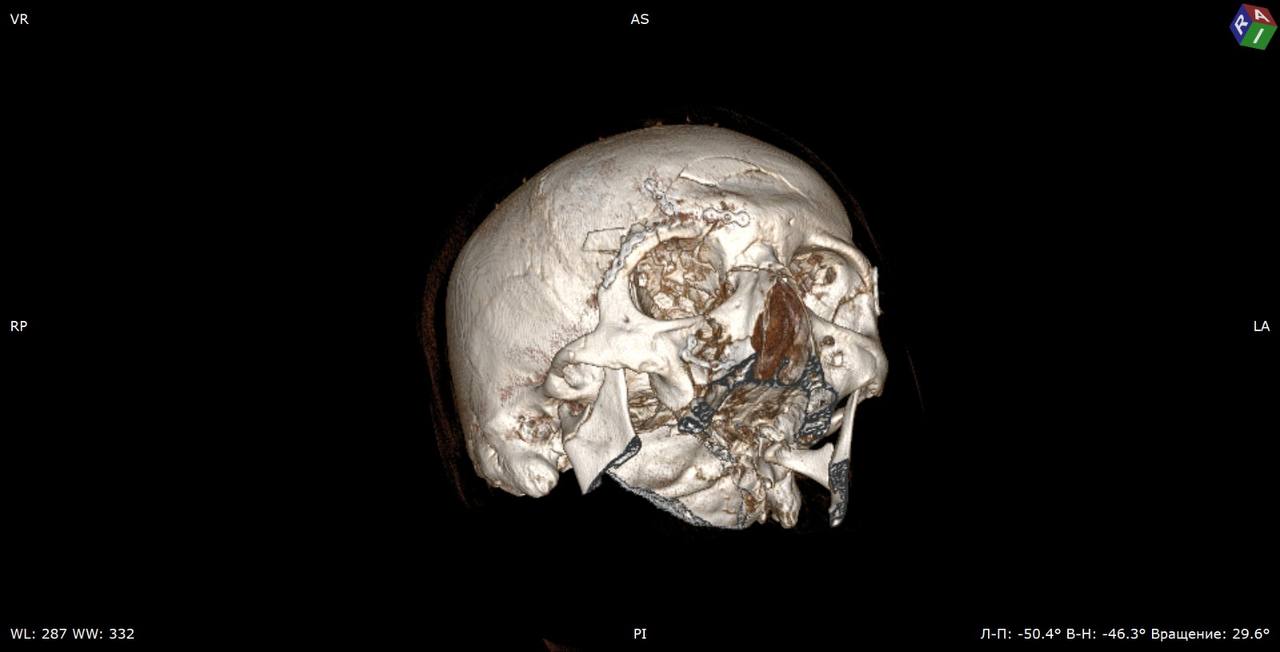

В отделение челюстно-лицевой хирургии ГБУЗ «Жуковская ОКБ» был экстренно доставлен 36-летний пациент, который упал с электросамоката и получил множественные переломы черепа — мозгового и лицевого отделов.

Как рассказали «Медицинской России» в больнице, среди полученных травм — переломы верхних, латеральных, нижних стенок глазниц, множественные переломы стенок верхнечелюстных пазух со смещением, правой скуловой дуги, ячеек решетчатой кости, верхней челюсти справа, крыловидных отростков клиновидной кости, ветвей нижней челюсти с двух сторон, тела нижней челюсти со смещением, лобной кости.

«Операция продолжалась более трех часов, в ходе нее врачам пришлось практически снять кожу головы, как скальп, зафиксировать все переломы специальными крепежами, а затем вернуть кожу на место, восстановив прежний облик», — рассказал хирург отделения челюстно-лицевой хирургии Тамаз Тотладзе.